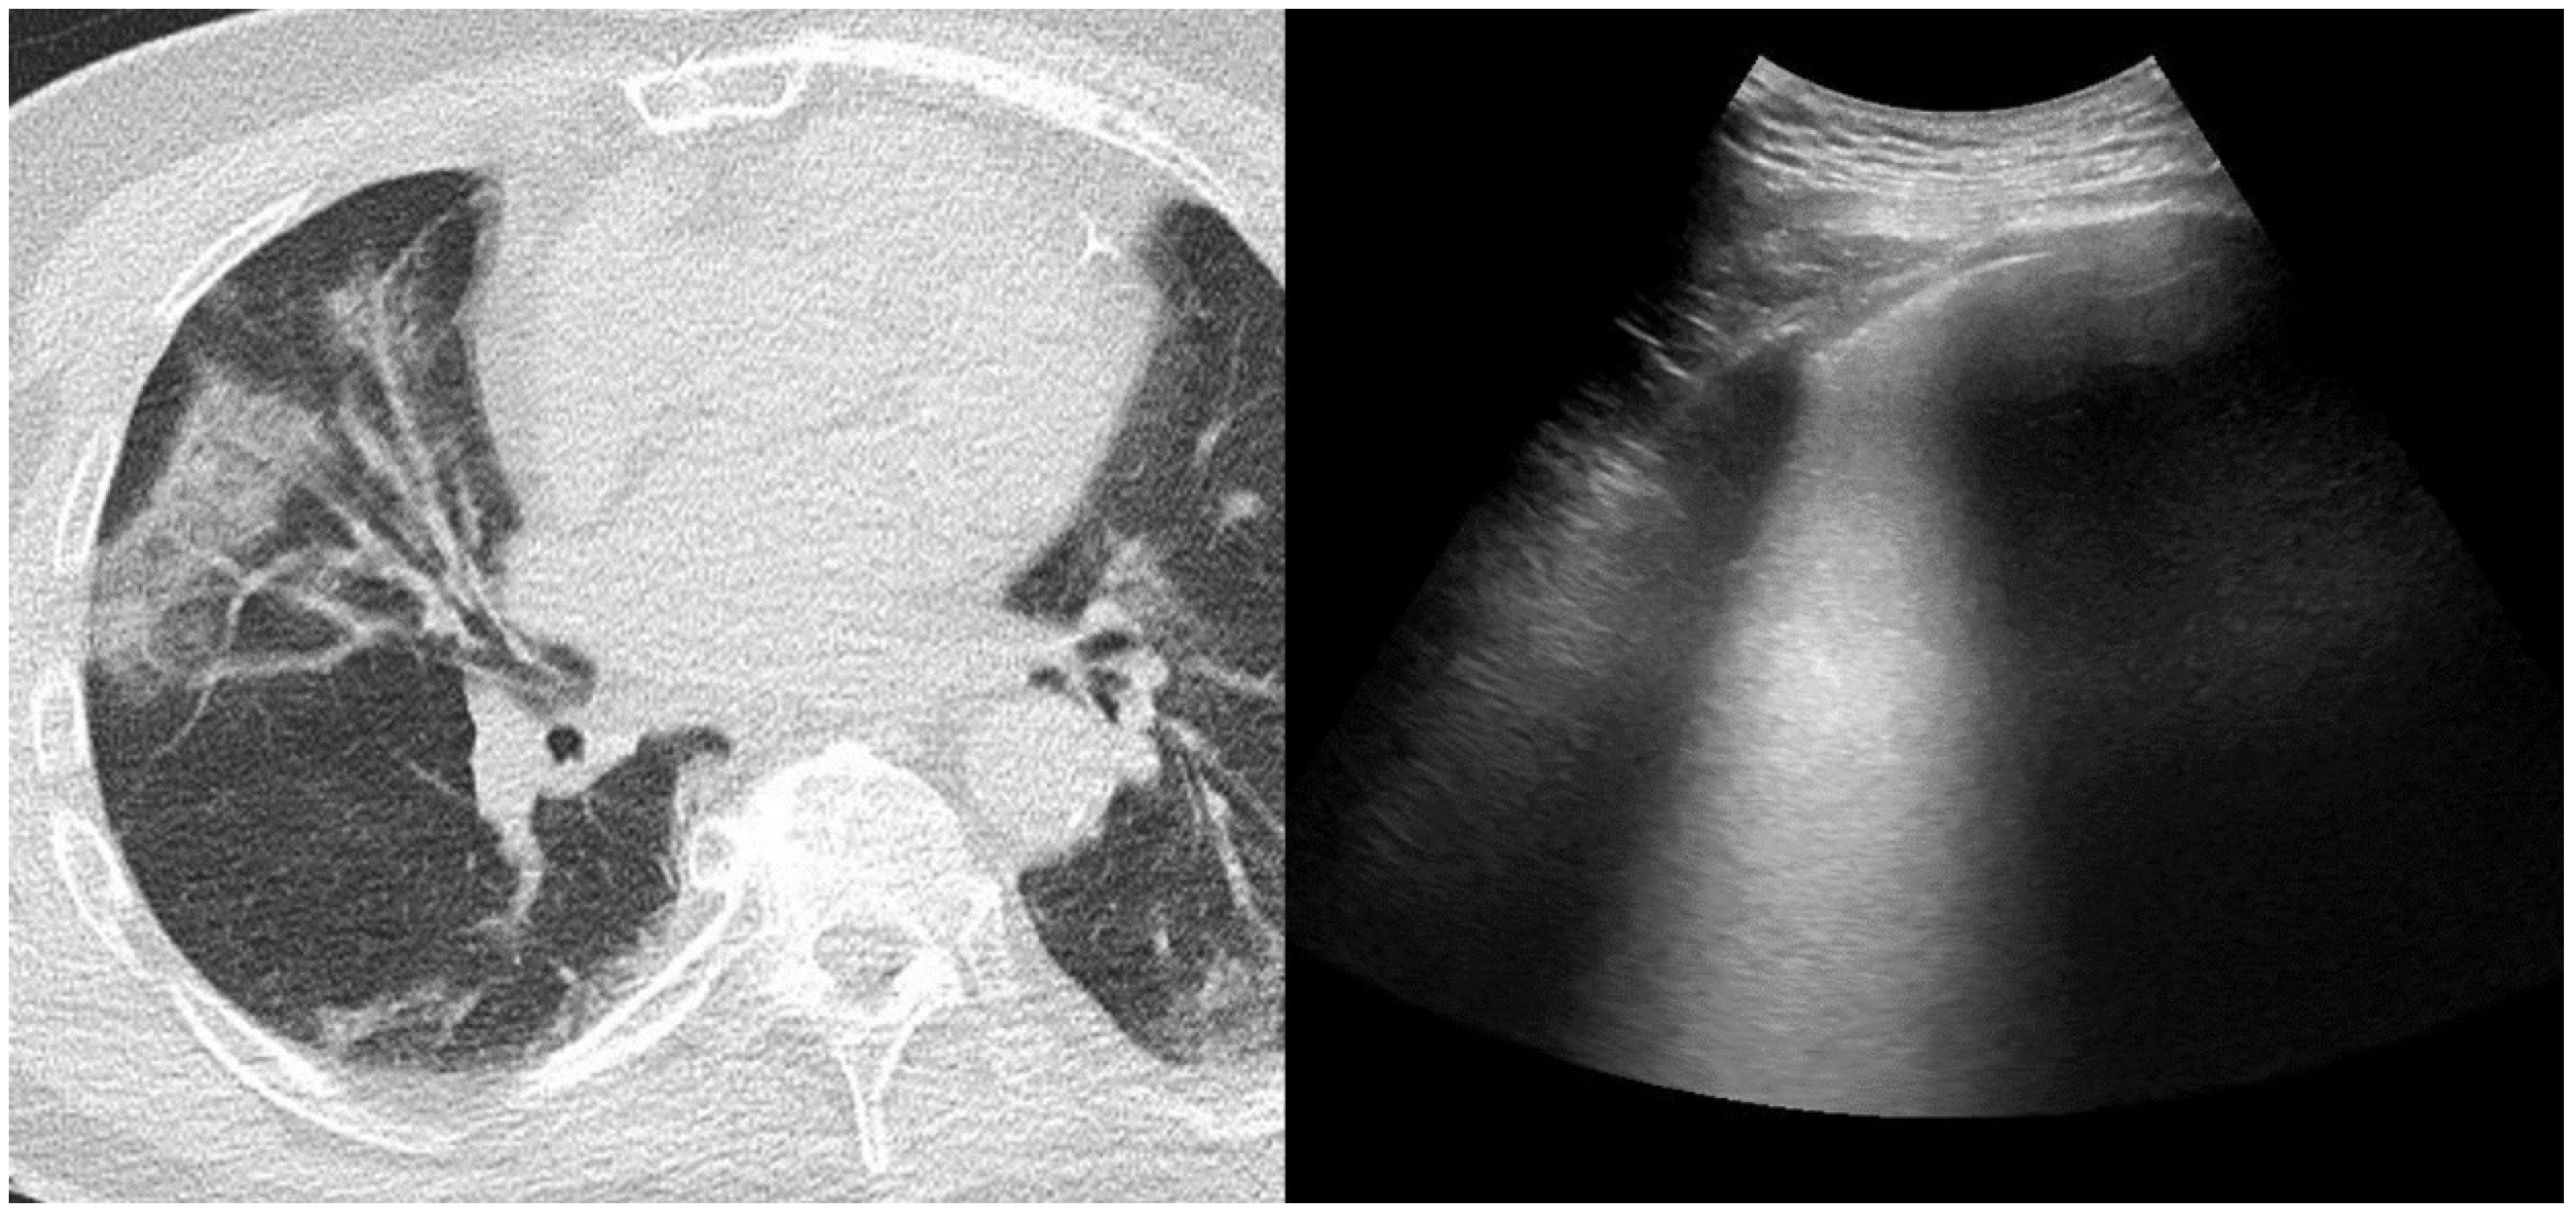

2.3. Chest Computed Tomography and Score Assessment

2.4. Lung Ultrasonography and Score Assessment

Appendix A